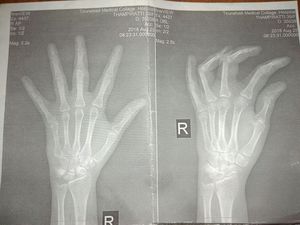

What is the diagnosis? Inflammation for about 8 days . Able to flex .but pain occurs when fully extending the middle finger

rheumatoid arthritics

Rheumatoid Arthritis. I have it. It sucks!!😑